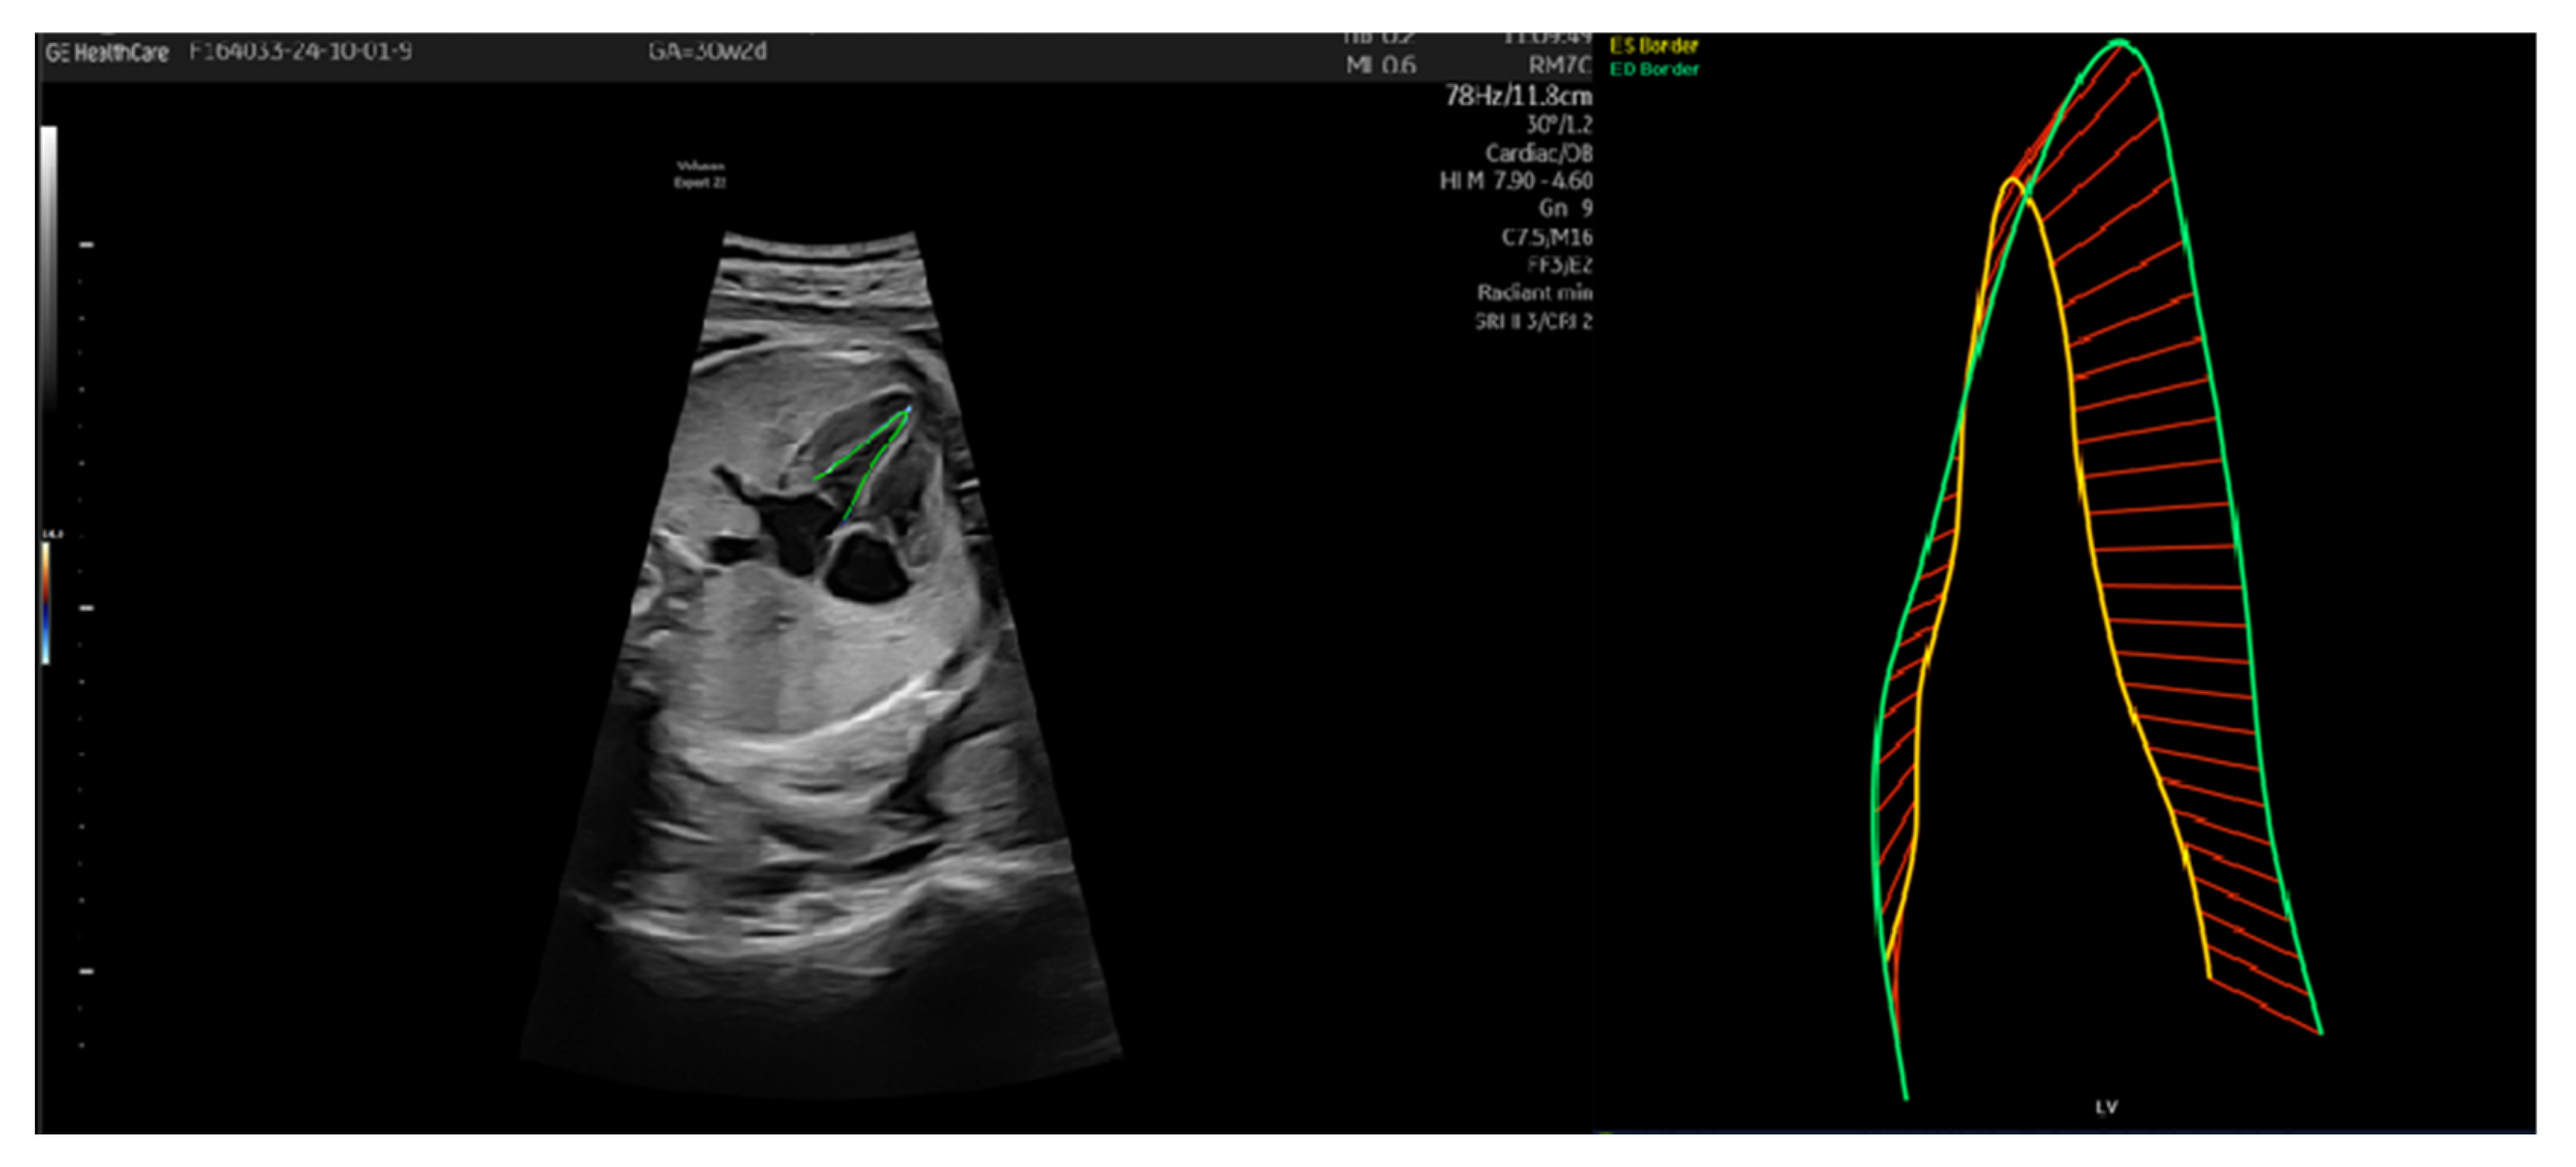

3.1. Patient Number 1

| Patient Number 1 | 26 Weeks | 28 Weeks | 30 Weeks | 36 Weeks |

|---|---|---|---|---|

| UA IP | 1.02 | 1.25 | 1.26 | 1.30 |

| UA IR | 0.66 | 0.72 | 0.72 | 0.74 |

| reverse flow UA | no | no | no | No |

| MCA IP | 1.72 | 1.65 | 1.91 | 1.64 |

| MCA IR | 0.81 | 0.77 | 0.82 | 0.75 |

| DV IP | 0.61 | no | no | No |

| right Ut A IP | 0.77 | 0.96 | 0.83 | 0.79 |

| left Ut A IP | 1.12 | 0.87 | 1.19 | 1.1 |

| LV endo GLS % | −21.48 | −28.27 | −23.71 | −11.5 |

| EF % | 62.53 | 70.93 | 72.76 | 69.1 |

| LV EDA cm2 | 0.9 | 1.25 | 1.32 | 1.39 |

| LV ESA cm2 | 0.49 | 0.53 | 0.58 | 0.71 |

| LV ESL cm | 1.35 | 1.57 | 1.64 | 1.9 |

| ESD bas cm | 0.53 | 0.7 | 0.69 | 0.7 |

| LV ESD mid cm | 0.39 | 0.42 | 0.35 | 0.3 |

| LV EDL cm | 1.72 | 2.16 | 2.13 | 2.1 |

| LV EDD bas cm | 0.73 | 0.71 | 0.89 | 1.0 |

| LV EDD mid cm | 0.58 | 0.67 | 0.73 | 0.7 |

| LV EDV ml | 0.44 | 0.68 | 0.74 | 0.8 |

| LV ESV ml | 0.16 | 0.2 | 0.2 | 0.27 |

| MAPSE l (lateral mitral annulus) cm | 0.37 | 0.53 | 0.39 | 0 |

| MAPSE s (septal mitral annulus) cm | 0.39 | 0.64 | 0.6 | 0.4 |

| FAC (fractional area change) % | 45.95 | 57.31 | 56.09 | 49.3 |